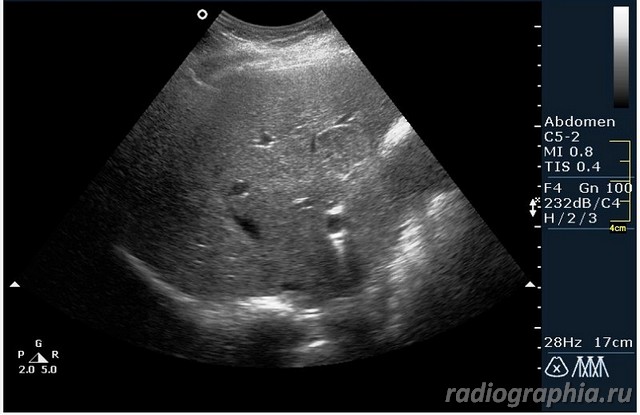

УЗИ печени. Женщина 37 лет. Жалобы на боли в эпигастрии; в печени обнаружено такое образование...

Считаю,что это опухоль,имеет неоднородную структуру,четкий контур,прорастает в сосуд(есть один такой скан) И,вообще,вся поверхность печени НЕСПОКОЙНАЯ,могут быть мелкие МТ.Интересно,что на КТ?

так и хочется назвать это метастазами но уж очень они красивые и доброжелательние по структуре (изоехогенные по отношению к структуре печени) и они больше компресирують чем проростают, склонен к ответу о доброкачественной гиперплазии. так что же на КТ?

Спсибо,но...вся печень какая-то неоднородная.